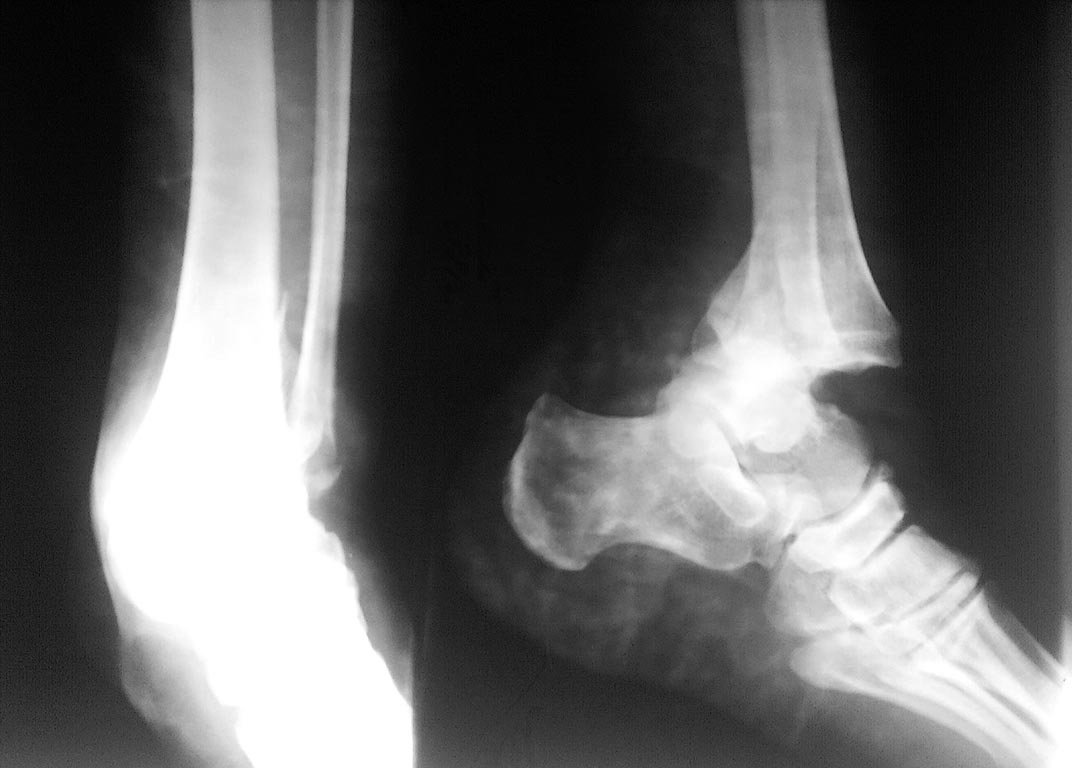

Здравствуйте. Операция 2 дня назад по дежурству, объем движений в голеностопном суставе полный.

Пациенту 35 лет. Ограничиться заменой длинных винтов либо делать реостеосинтез малоберцовой кости?

1. Нет репозиции обеих лодыжек.

Реостеосинтез обеих лодыжек, устранить смещение медиальной лодыжки и синтез иным способом (ваши спицы слишком тонкие), что касается латеральной лодыжки менять шурупы, при необходимости и пластину.

А по-моему остеосинтез сделан нормально, переделывать особой нужды нет. Верхние 3 винта пластины расположены позади большеберцовой кости, их можно оставить до удаления всей пластины. Поменять только 2 нижних и, может быть, доставить еще один винт во второе снизу отверстие. Или переставить туда винт из третьего снизу отверстия, который проходит через область перелома.

Лучше переделать. Наружная укорочена, винты огромны, направление их?(полный обьем?) пластина сзади предпочтительней(не реконструктивная). Внутренняя не критично, но не эстетично. Позиционный винт? Хотя можно и оставить. Качество жизни для всех разное, особенно в России.

На представленных рентгенограммах видим черезсиндесмозный перелом малоберцовой кости, перелом внутренней лодыжки, задний вывих таранной кости и скорей всего перелом заднего края.

что сделано:

1. выполнен остеосинтез малоберцовой кости - .

но нет межфрагментарного винта, удерживающего обломки малоберцовой кости.

2. треть трубчатая пластина не отмоделирована.

3. остеосинтез малоберцовой кости можно было выполнить винтом и спицей киршнера. Этого более чем достаточно.

4. Если возникли сомнения о сохранности межберцового синдесмоза - почему не поставлен позиционный межберцовый винт.

Однозначно реостеосинтез. Повторная репозиция и фиксация первоначально стягивающим винтом. Пластину использовать эту же, только отмоделировать и опустить на одно отверстие, чтобы в дистальном отломке держалась на 2х винтах. Винты брать покороче и в сустав не вводите. Для того, чтобы устанавливать или нет позиционный винт можно проверить состоятельность синдесмоза однозубым крючком (здесь травма чрезсиндесмозная; при надсиндесмозных - устанавливать всегда). Установите хуже не будет, только нужно будет удалить через 2 месяца, чтобы не образовался синостоз.

Что касается внутренней лодыжки, лучше ничего не переделывать - фрагмент очень маленький, хуже сделаете. На будущее если делаете по Веберу, спицы нужно взять немного потолще (или на рентгене просто кажется что они тонкие?)

Задний край ББК менее 25% - он не фиксируется, но вывести его желательно гипсовой лонгетой.

На счет дальнейшей тактики у нас в отделении тоже мнения разошлись (сообственно, поэтому я и воспользовался форумом). Лично я, считаю, что синтез выполнен не так плохо, как неэстэтично. Внутренняя, да и наружная лодыжка недорепонированы, но, по-моему, некритично. Линия сустава параллельна, задний край составляет менее 1/4 суставной поверхности, синдесмоз интраоперационно был цел (со слов хирурга). Конечно, без внешней иммобилизации перелом вести нельзя.

Реостеосинтез обязателен. Есть подвывих стопы кнаружи за счёт неполной репозиции медиальной лодыжки. Если оставлять так, то будет артроз, будут ограничение функции, а пациент молодой. Лучше сделать сейчас:

-реостеосинтез мед. лодыжки по Веберу ("кортикал в кортикал")

-репозиция малоберцовой удовлетворительная, только поменять винты и обязательно "задавить вилку" межберцовым винтом

-задний край оценить сложно, но по-моему нужен его остеосинтез( чтобы третий раз не переделывать).